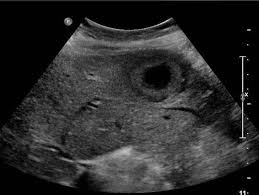

- 간암, 간종양: 실질 내부에 덩어리 유무 탐색